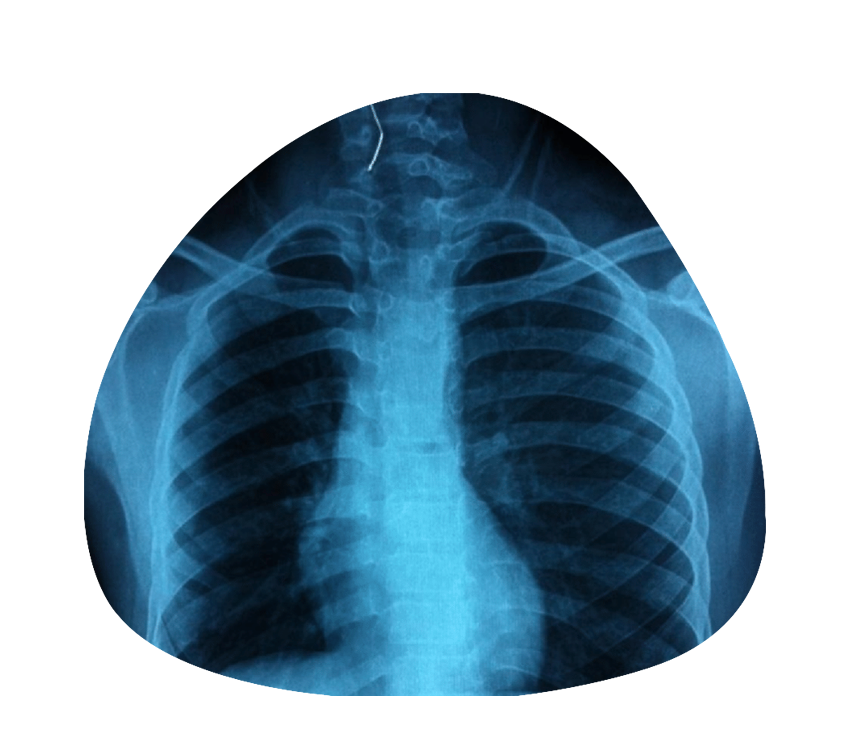

Digital X RayOur state of the art machines provides accurate and reliable reports

Digital X RayOur state of the art machines provides accurate and reliable reports -

Accurate DiagnosisWith Advanced Equipment.Excepteur sint occaecat cupidatat non proident, sunt in culpa qui mollit anim id est laborum.

Accurate DiagnosisWith Advanced Equipment.Excepteur sint occaecat cupidatat non proident, sunt in culpa qui mollit anim id est laborum.